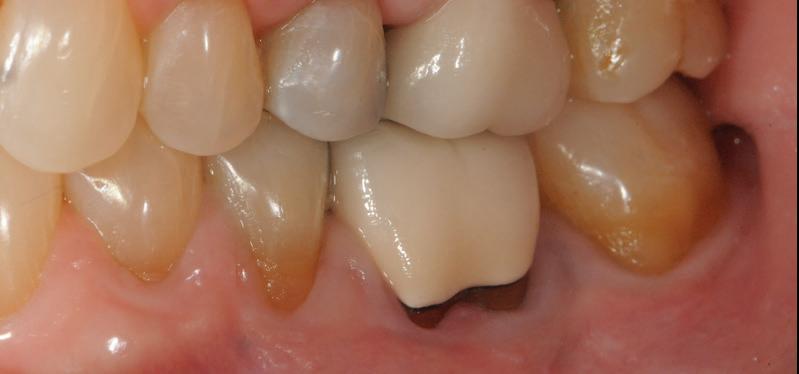

-year follow-up radiographs showed evidence of bone fill. Clinically, maturation of interdental tissue is evident as well.

-year follow up clinical photos are demonstrating stability of bone, lack of facial and minimal interproximal recession.

-year follow-up radiographs showed evidence of bone fill. Clinically, maturation of interdental tissue is evident as well

-year follow up clinical photos are demonstrating stability of bone, lack of facial and minimal interproximal recession. Stability of the bone radiographically is evident as well.

® did not only enhance the outcome of this challenging case, but ensured its st ability

® did not only enhance the outcome of this chal lenging case, but ensured its st ability